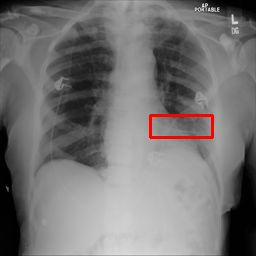

Deployments of artificial intelligence in medical diagnostics mandate not just accuracy and efficacy but also trust, emphasizing the need for explainability in machine decisions. The recent trend in automated medical image diagnostics leans towards the deployment of Transformer-based architectures, credited to their impressive capabilities. Since the self-attention feature of transformers contributes towards identifying crucial regions during the classification process, they enhance the trustability of the methods. However, the complex intricacies of these attention mechanisms may fall short of effectively pinpointing the regions of interest directly influencing AI decisions. Our research endeavors to innovate a unique attention block that underscores the correlation between 'regions' rather than 'pixels'. To address this challenge, we introduce an innovative system grounded in prototype learning, featuring an advanced self-attention mechanism that goes beyond conventional ad-hoc visual explanation techniques by offering comprehensible visual insights. A combined quantitative and qualitative methodological approach was used to demonstrate the effectiveness of the proposed method on the large-scale NIH chest X-ray dataset. Experimental results showed that our proposed method offers a promising direction for explainability, which can lead to the development of more trustable systems, which can facilitate easier and rapid adoption of such technology into routine clinics. The code is available at www.github.com/NUBagcilab/r2r_proto.